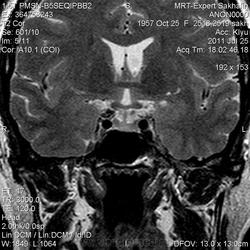

Как мы "динамичим"гипофиз

Женщина.6 лет назад выявлено образование левой доли нейрогипофиза.Пришла на контроль.

Постконтраст

Мне самой показался случай не совсем ясным, но динамик четко показывает участок с отставанием в контрастировании, воронка смещена вправо-о чем  думать бедному начинающему специалисту?